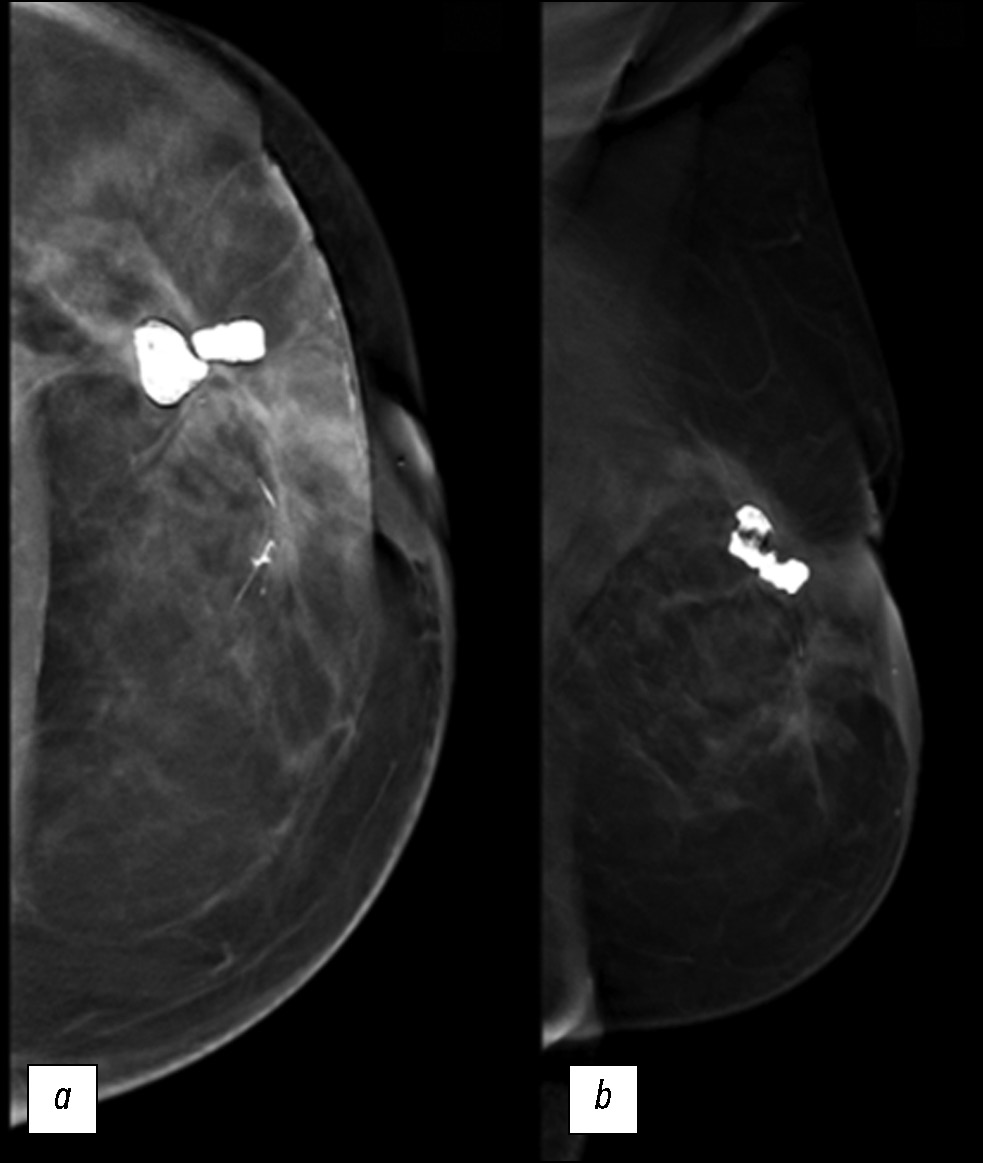

We describe a rare case of secondary breast angiosarcoma in a 72-year-old woman with a history of breast cancer who presented to our clinic with a painless palpable mass in the outer upper quadrant of the left breast. The diagnosis required a multidisciplinary approach involving a senologist, anatomopathologist, and oncologist. Imaging modalities such as mammography, ultrasonography, and magnetic resonance imaging made it possible to assess the extent of the tumor, lymph node involvement, and distant metastases. The diagnosis was confirmed by a tissue biopsy. Herein, a rare case is presented, with the main educational purpose of describing the clinical presentation and complex diagnostic evaluation and discussing the differential diagnosis and management. Indeed, secondary mammary angiosarcoma is a rare and aggressive neoplasm, and understanding its unique features is essential for clinical decision-making and patient outcomes. The tumor has a worse prognosis because of its late diagnosis, higher risk of rapid distant spread, and limited treatment options. Such cases require close monitoring, aggressive strategies, and supportive care.